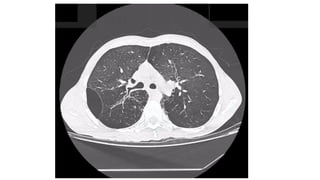

DIAGNOSTICO

• Datos clínicos y la radiografía de tórax,

• Confirmatorio  tac de alta resolución

Dependiendo de la etapa en que se pesquisa se vera una variada

gama de severidad de lesiones.

DIAGNOSTICO • Datos clínicosy la radiografía de tórax, • Confirmatorio  tac de alta resolución Dependiendo de la etapa en que se pesquisa se vera una variada gama de severidad de lesiones.